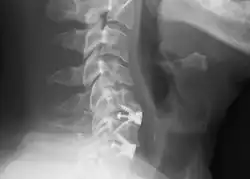

![]() Radiografía cervical lateral que muestra las fijaciones de C5C6 y C6C7, después de una discectomía y fusión cervical anterior. | ||

La discectomía y fusión cervical anterior es un procedimiento quirúrgico para tratar la compresión de la raíz nerviosa o la médula espinal mediante la descompresión de la médula espinal y las raíces nerviosas de la columna cervical con una discectomía, seguida de una fusión intervertebral para estabilizar las vértebras correspondientes.[1] Este procedimiento se utiliza cuando otros tratamientos no quirúrgicos han fallado.